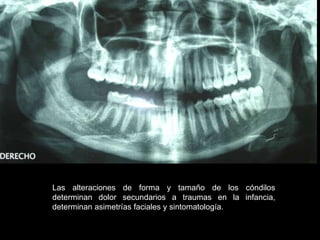

Las alteraciones de forma y tamaño de los cóndilos

determinan dolor secundarios a traumas en la infancia,

determinan asimetrías faciales y sintomatología.